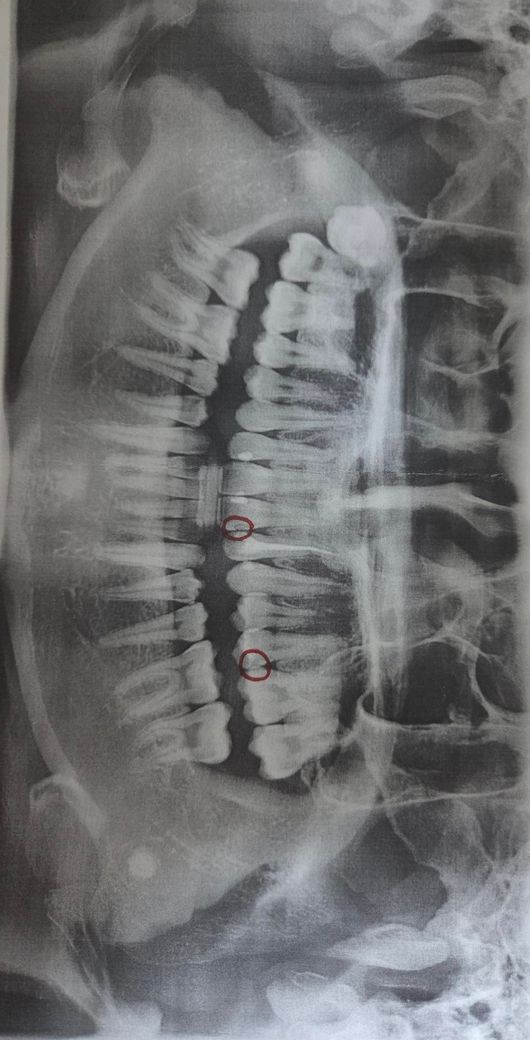

얼마 전 치과를 방문했는데 왼쪽 턱뼈 근처에서 흰색 동그란 게 발견되었습니다. 인터넷에 찾아보니 타석증일 수도 있다는데 병원을 가보는 게 좋을까요?

• 2번 째 사진

제공하신 엑스레이만으로 단정할 수는 없지만, 보이는 소견만 기준으로 설명드리면 다음 가능성을 고려합니다.

1. 타석증 가능성

침샘(특히 악하선) 타석은 엑스레이에서 비교적 경계가 분명한 원형 또는 타원형 고음영으로 보일 수 있습니다. 위치가 턱뼈 안쪽, 하악 하연 근처라면 타석증 가능성은 배제할 수 없습니다. 다만 모든 타석이 엑스레이에 보이는 것은 아닙니다.

2. 다른 가능성

림프절 석회화, 정맥 석회화(phlebolith), 치성 병변, 골내 석회화 병변 등도 유사하게 보일 수 있습니다. 증상이 없더라도 우연히 발견되는 경우가 흔합니다.

현재로서는 “타석증일 수는 있으나, 엑스레이 단독으로 확진할 소견은 아니다” 정도로 판단하는 것이 보수적입니다.